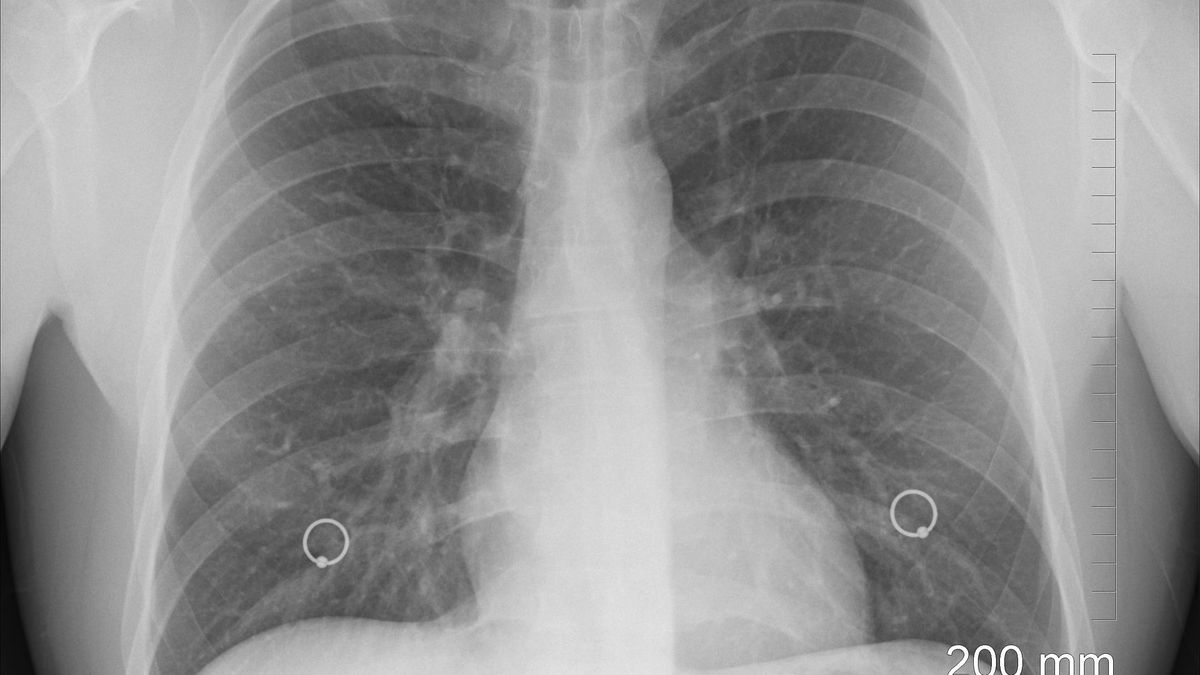

Sześcioletni odsetek przeżyć jest jednak diametralnie niższy niż w przypadku innych nowotworów złośliwych. Ze statystyk wynika, że tylko 20 proc. wszystkich przypadków raka płuca diagnozowanych jest na etapie rozwoju na tyle wczesnym, by możliwe było operacyjne usunięcie guza. Problem stanowi już sama diagnostyka. Nowotwór ten długo nie daje objawów i najczęściej rozpoznawany jest przypadkowo, np. podczas badań medycyny pracy. Eksperci nie mają ponadto wątpliwości, że polscy pacjenci nie mają równego dostępu do nowoczesnej diagnostyki m.in. ze względu na zbyt małą liczbę patomorfologów. W efekcie na wynik badań pacjent może czekać kilka tygodni.